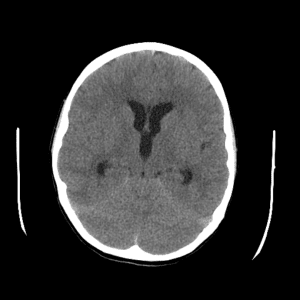

Non-traumatic Head CT Cases

Classic Cases

Includes classic examples of cases commonly seen on call.